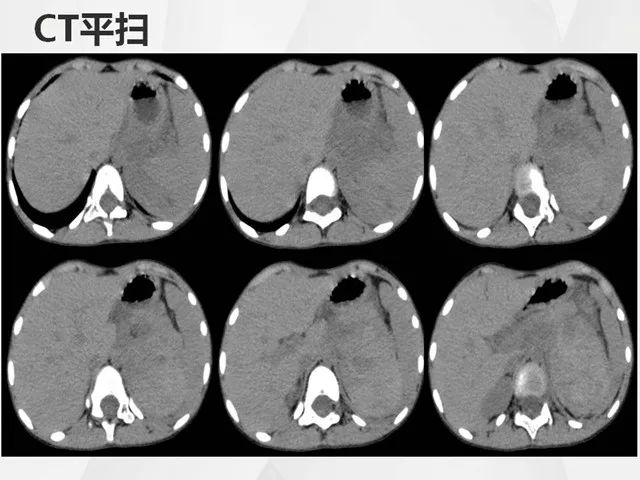

肾上腺嗜铬细胞瘤ct诊断与鉴别诊断

图片尺寸1080x661